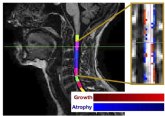

04/11/2019 Un nuevo método para medir la atrofia de la médula espinal se incorpora a un ensayo sobre la esclerosis múltiple